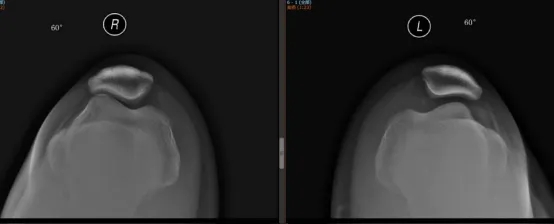

接診的運(yùn)動醫(yī)學(xué)科主任醫(yī)師韋釗嵐博士查體后發(fā)現(xiàn),小張的膝關(guān)節(jié)在屈膝30°位時(shí),髕骨向外側(cè)滑動的幅度很大,向外推動髕骨時(shí),膝關(guān)節(jié)會引發(fā)很明顯的疼痛,再結(jié)合她的X片,考慮為髕骨不穩(wěn)定導(dǎo)致的膝關(guān)節(jié)復(fù)發(fā)性髕骨脫位。

髕骨脫位就是膝關(guān)節(jié)屈伸過程中,髕骨向膝關(guān)節(jié)外側(cè)完全脫出。發(fā)生髕骨脫位的病人一般都會有膝關(guān)節(jié)的外翻或者小腿外旋扭傷的病史。